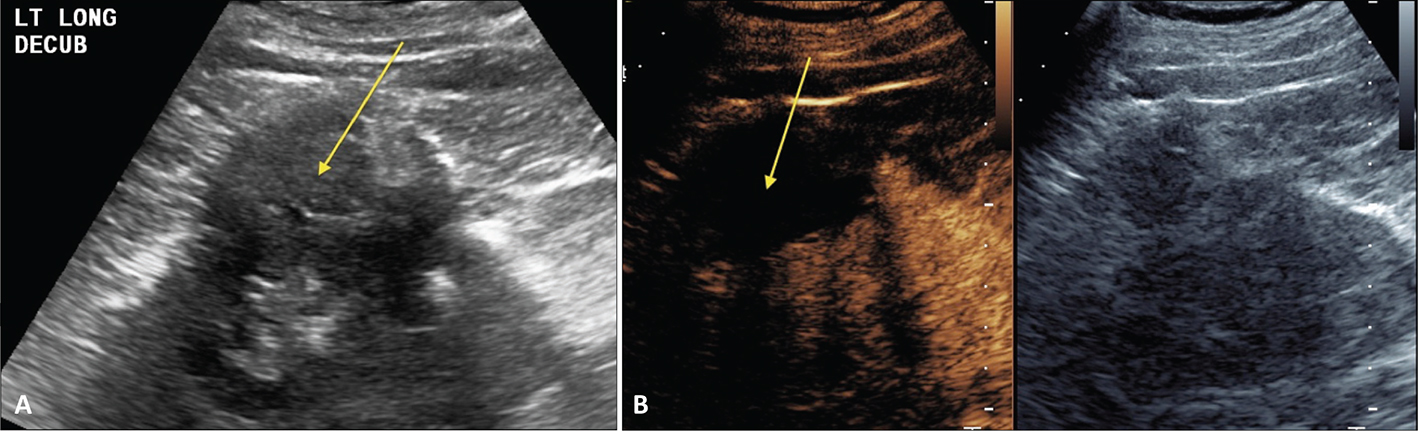

Figure 6 demonstrates the advantage of CEUS over CT. Because CEUS has a contrast-only image, small amounts of enhancement are easily identified. On CT (as well as MRI) there is signal from the associated soft tissues, making it difficult to identify small amounts of enhancement.

Figure 6. Images 6 months post-RFA of an RCC. (A) CT scan without contrast in this patient with renal failure. The ablated RCC (arrows) has significant attenuation making it difficult to determine if there is residual tumor. Even if contrast is administered, the background tissue makes it difficult to identify small areas of enhancement. (B) CEUS scan at the same 6-month post-RFA time point as the CT in (A). Ultrasound contrast agents can be used in patients with renal failure. Note that the excellent tissue suppression of CEUS allows for a contrast-only image, making it easy to see that there is no enhancement and no residual or recurrent tumor.